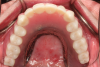

The optical scan files are imported into a dental-specific software, where a framework can be designed using a wizard-like function. Because the stud-style abutment maxillary overdenture is a tissue-supported prosthesis with implant-retention, it is important to carefully design the suprastructure to ensure long-term success of the restoration (Figure 8). A clinician and technician are often faced with a catch-22, because the maxillary hard palate is the primary support/stability factor for the maxillary arch, yet the patient is often motivated by having as little palatal coverage as possible. To meet both expectations, the patient should be informed of the goals of the prosthesis and the benefits and risks of eliminating palatal coverage completely versus minimizing palatal coverage. The former creates a "ridge-runner prosthesis," while the latter creates a "horseshoe prosthesis" with an emphasis on placing as much of the suprastructure on the primary hard palate as possible.

Fig 8. Optical

scans are imported into dental-specific software and framework designed to ensure as much palatal

coverage as possible is achieved and retentive meshwork surrounding abutment housings

Figure 8